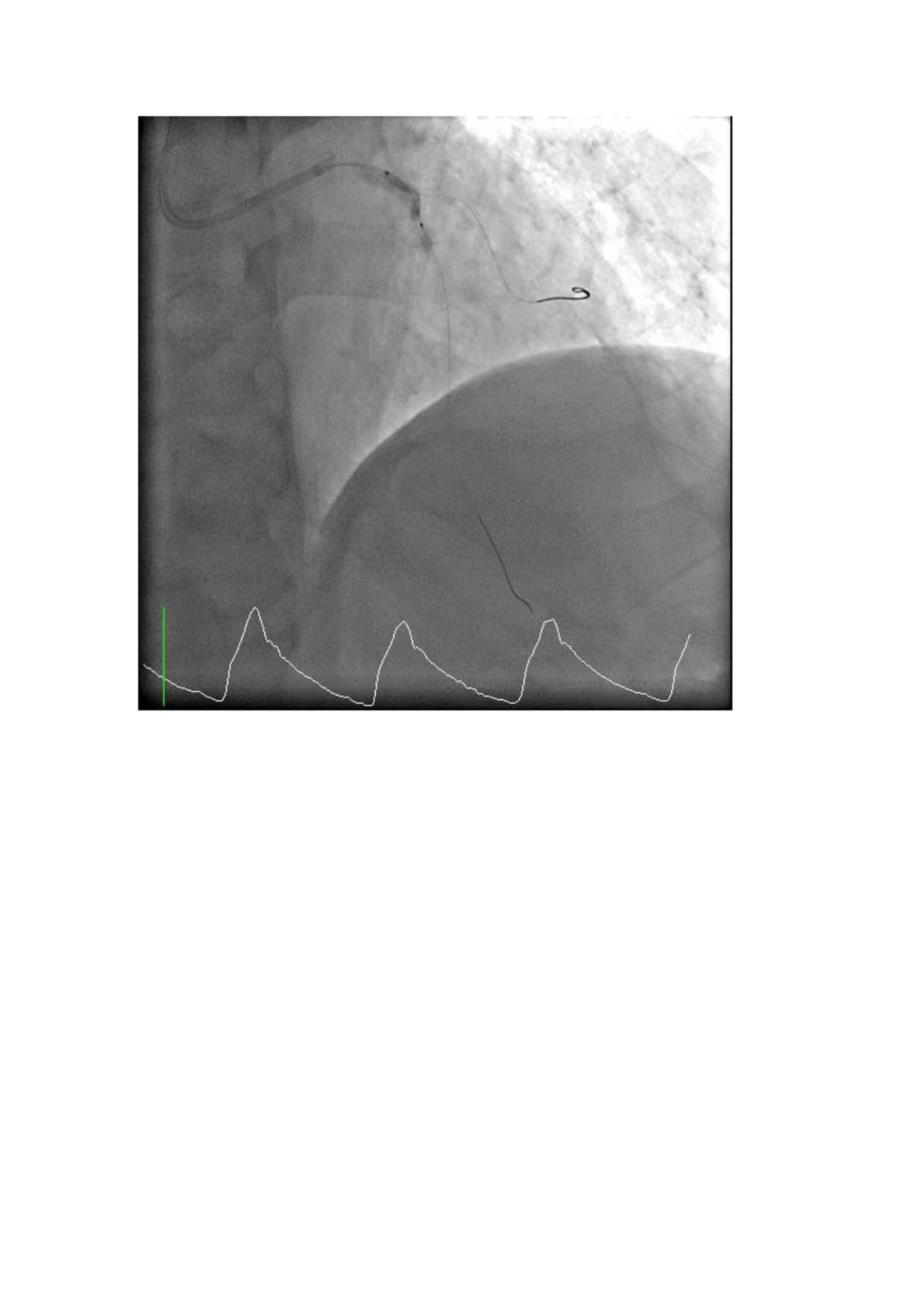

病史摘要:1.患者,男,80岁;2 .主诉:发作性胸闷、胸痛5年余,加重一月余3 .查体:神清、气平,全身皮肤未见黄染,全身浅表淋巴结未及肿大。双侧瞳孔等大等圆,对光反射存在。口唇无绢,伸舌居中,颈软,气管居中,颈静脉无怒张,双侧呼吸音清,双肺未闻及干湿罗音。心率83次/分,律齐,未闻及病理性杂音,血压134/8OmmHg。腹软,无压痛、无反跳痛。肝脾肋下未及。双下无肢浮肿。正常生理反射存在,病理反射未引出。4 .辅检:2016/06/21;冠状动脉造影术PCl术,LM:未见明显狭窄:LAD:近段开始弥漫性病变,80-95%狭窄;LCX:弥漫性病变,钙化,中段局部60%狭窄;RCA:近段支架内内膜增生,中段局部80%狭窄,远段闭塞。右冠植入3.0*15mmRES0LUTE支架。48小时主治医师诊断:冠状动脉粥样硬化性心脏病、不稳定型心绞痛、陈旧性下壁心肌梗死、RCA-PCl术后、心功能II级、高血压病八